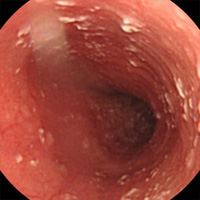

캔디다 식도염

• 캔디다 감염증에 의해 발생한 식도염을 캔디다 식도염이라고 합니다. 보통 면역억제제 및 광범위 항생제나 스테로이드를 사용할 때, 당뇨병, 알코올 중독증, 영양결핍, 고령 등으로 면역 기능이 감퇴하였을 때 자주 발생합니다. 캔디다 식도염은 내시경검사에서 식도 점막에 다발성의 흰색 또는 황색 플라크(plaque)가 부착되어 있는 모양을 보고 쉽게 진단 할 수 있습니다.